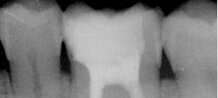

Cas clinique : Dentisterie Adhésive / Dentisterie Esthétique

Les couronnes et bridges représentent le traitement classique (et historiquement le plus ancien) de restauration prothétique des dents fortement délabrées et/ou absentes. Depuis une quinzaine d’années et l’avènement de techniques moins invasives et souvent plus esthétiques (cf. dentisterie adhésive et esthétique, traitements implantaires), leurs indications vont en diminuant. Cependant, ces options thérapeutiques demeurent extrêmement fiables et dans certains cas, incontournables.